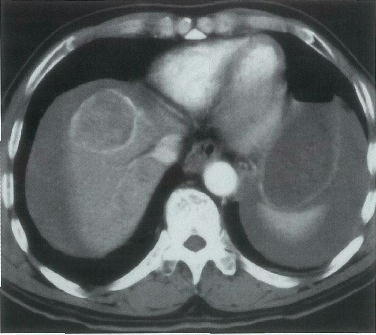

64歳の男性。昨晩から持続する腹痛を主訴に来院した。10年前に肝疾患を指摘された。意識は清明。顔色は不良である。脈拍 112/分,整。血圧 84/60mmHg。血液所見:赤血球 189万,Hb 5.8g/dl,白血球 9600。腹部単純CT(A,B)と造影CT(C,D)とを別に示す。

輸血を開始した後に行うのはどれか。

正解 a

診断 肝癌の腹腔内破裂